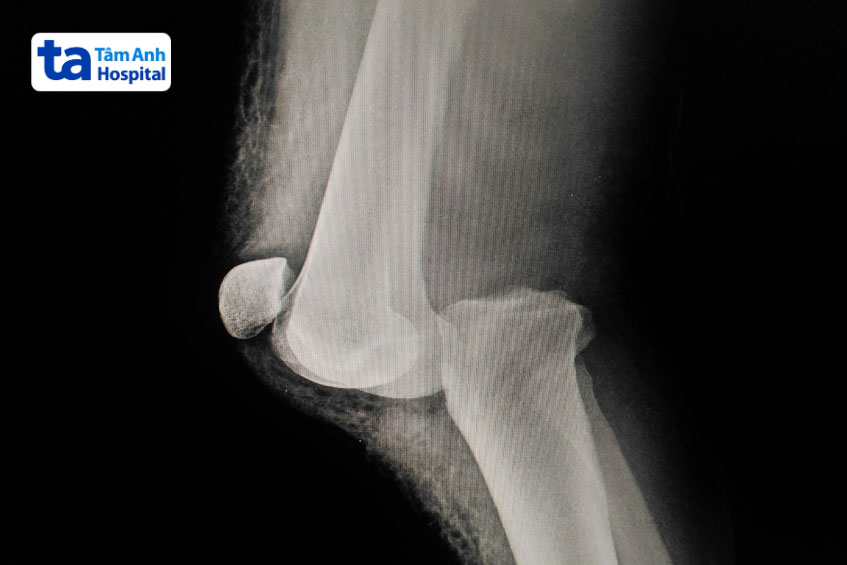

Người bệnh có thể cần chụp X-quang hoặc MRI để xác định mức độ nghiêm trọng của trật khớp. Sau đó bác sĩ sẽ nắn sai khớp, điều chỉnh và đưa các xương ở khớp gối về vị trí ban đầu. Các phương pháp điều trị có thể bao gồm nẹp, bó bột, phục hồi chức năng…